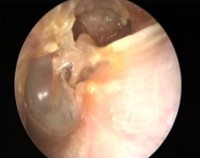

• Отомикроскопия. При объективном осмотре просвета слухового канала определяется небольшой объем гнойных масс, краевой дефект в расслабленной части, ретракция барабанной перепонки, признаки ее воспаления. На медиальной стенке визуализируются изменения слизистой оболочки в виде ее гиперплазии или полипоза.